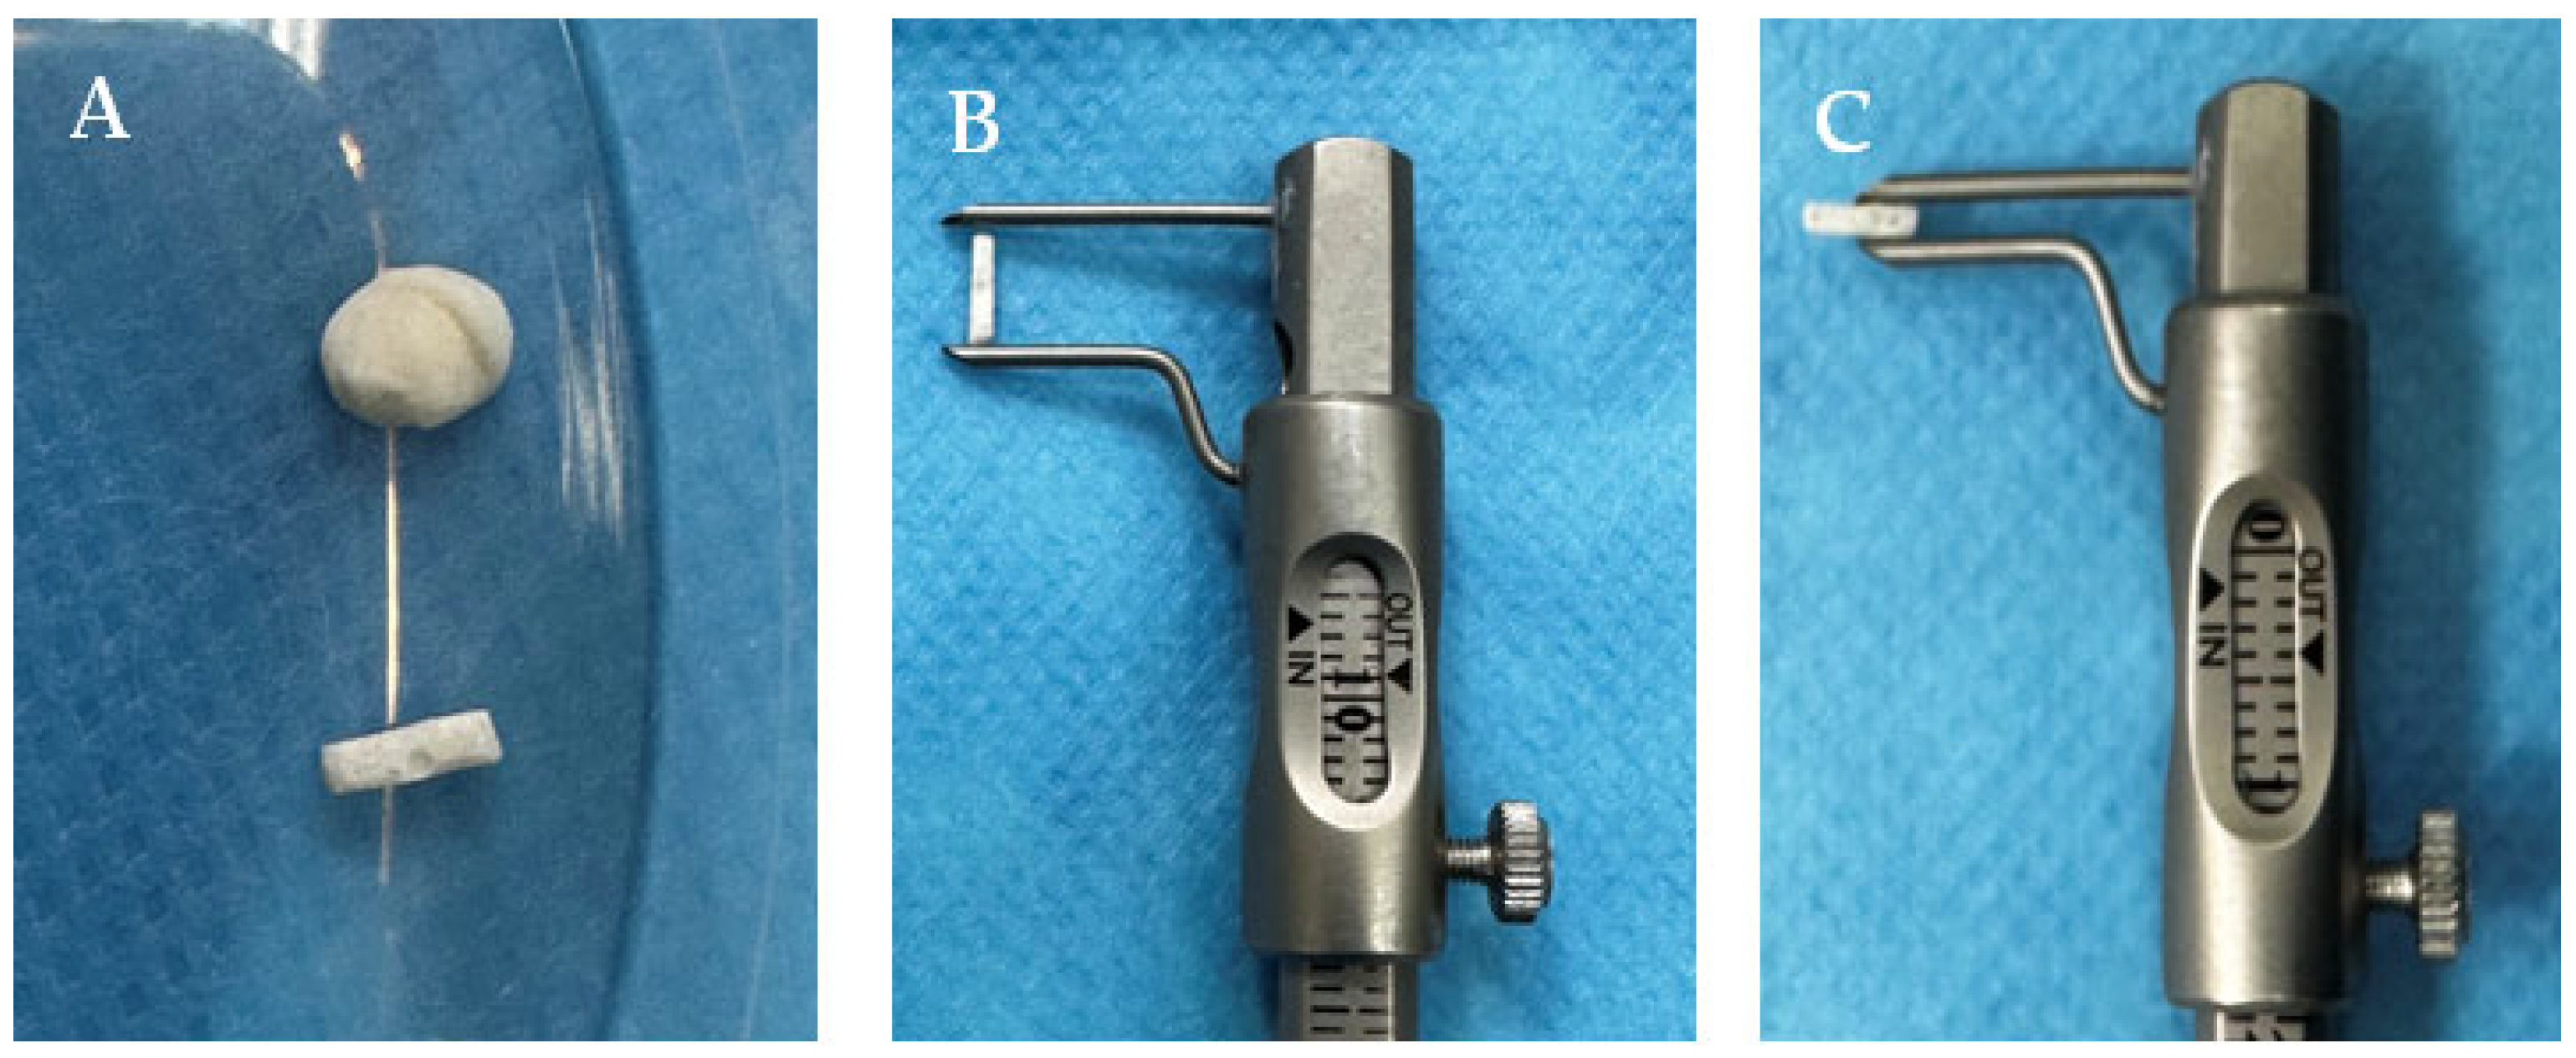

2.5. Study Design

2.6. Biomaterial Implantation

2.6.1. Subcutaneous

2.6.2. Intramuscular/Perimuscular